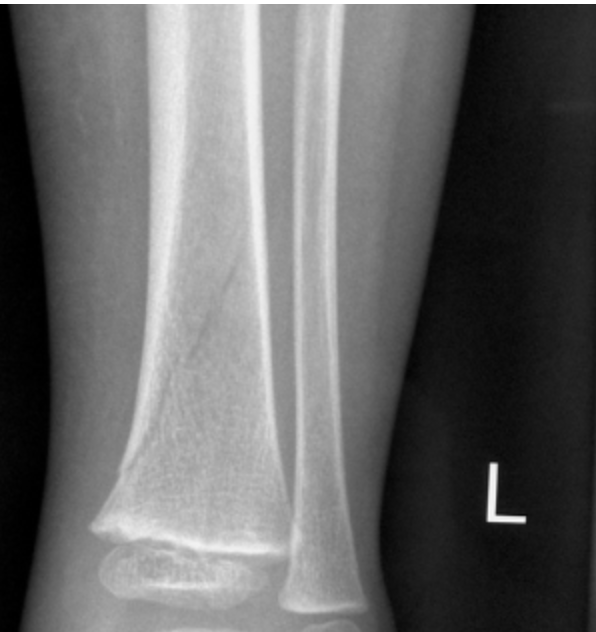

What age and mechanism might you see this?

toddler, 2yo, running and tripping